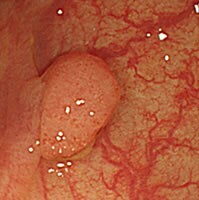

ポリープとは?

ポリープとは粘膜の表面に盛り上がってできるもので、病名ではなく形態を示します。ポリープには良性のものと悪性のものがあり、大腸の場合は良性と言っても悪性化することのない過形成性ポリープと、見つかった時は良性でも、そのまま切除せずに放置することで数年後にがんに変わる可能性のある大腸腺腫があります。大腸腺腫ががんに変わるリスクや時期を予測することはできません。大腸カメラ検査での早期検診、がん化する前の段階でポリープを取り除くことが大切です。

大腸ポリープ(NBI、狭帯光観察と大腸ポリープ切除)

大腸ポリープ(NBI、狭帯光拡大観察)